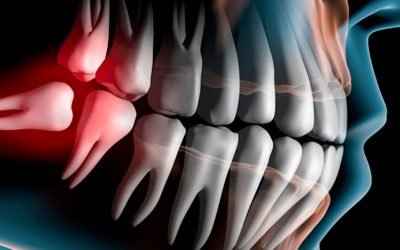

Chirurgia orale

Chirurgia orale vicino Legnano Dental Equipe si occupa di Chirurgia Orale a San Vittore Olona,...